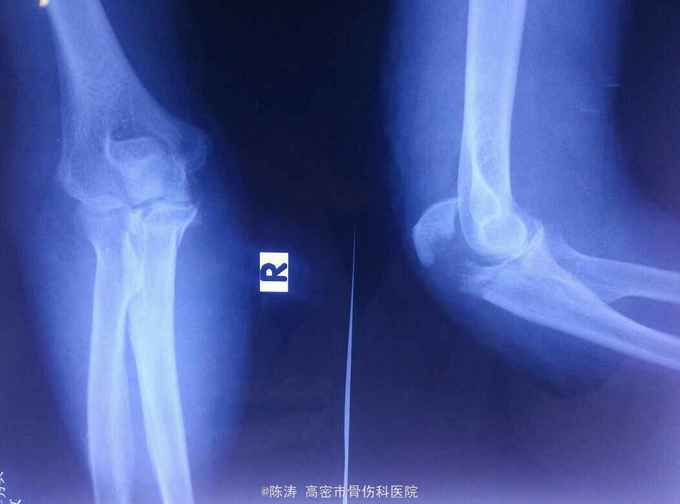

右肘部外伤,肿痛伴活动受限1天。一天前不慎摔倒,右肘部着地,伤后即出现肿胀、疼痛伴活动受限。来诊。患者老年女性,高血压病史20年余,自服降压0号、卡托普利,控制可。

右肘部明显肿胀,尺骨鹰嘴处压痛,触及骨擦感及异常活动,肢端血运、感觉及指动正常。

1.右尺骨鹰嘴骨折;2.高血压病。入院后完善各项必要检查,暂给予消肿止痛、活血化瘀及对症支持治疗,择期手术治疗。